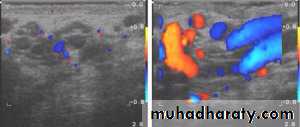

VARICOCELE

It is a varicose dilatation of the veins draining the testis ( abnormal dilatation of the pampiniform plexus)Most varicoceles present in adolescence or early adulthood

Usually on the left.

Investigations: Scrotal Doppler U/S